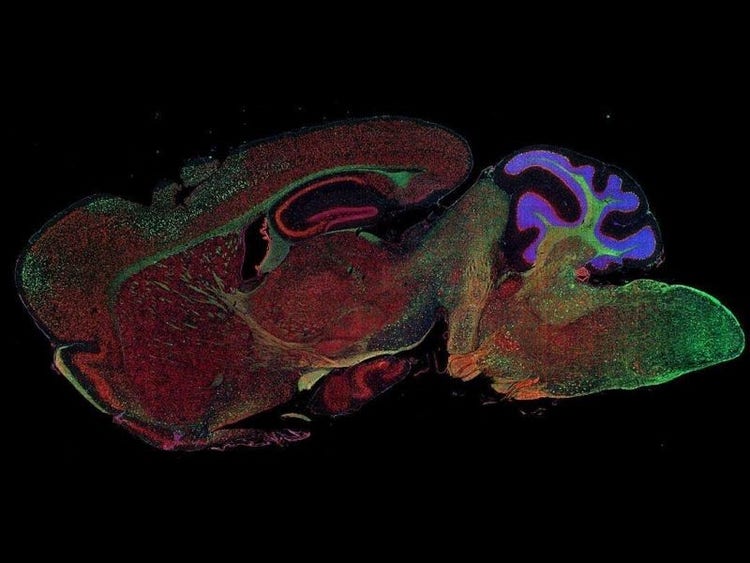

Fluorescence imaging of a mouse brain

Cette vue d’un cerveau de souris est en réalité constituée par l’assemblage d’une multitude d’images prises par imagerie de fluorescence.

Le scientifique britannique Sir George G. Stokes a d’abord constaté que la fluorine minérale devenait fluorescente lorsqu’elle était éclairée par une lumière ultraviolette, et il a inventé le mot « fluorescence ». Stokes a remarqué que la lumière fluorescente présentait des longueurs d’onde supérieures à celles de la lumière d’excitation, un phénomène aujourd’hui connu sous le nom de « déplacement de Stokes ». La microscopie de fluorescence est une excellente méthode pour étudier une matière qui peut devenir fluorescente soit sous sa forme naturelle (appelée fluorescence primaire ou autofluorescence), soit lorsqu’elle est traitée avec des produits chimiques qui peuvent devenir fluorescents (appelée fluorescence secondaire).